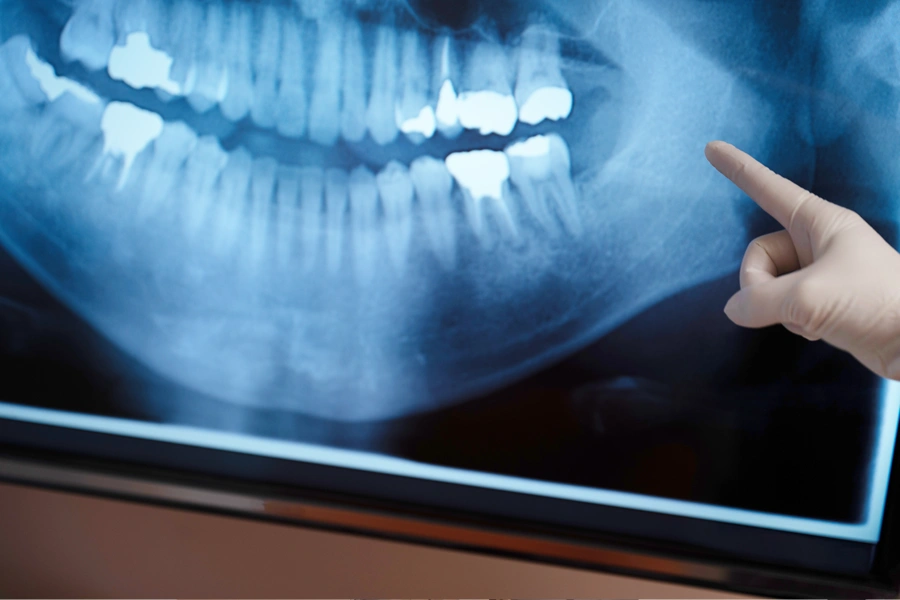

歯科用CT

当院では、インプラント治療の成功に不可欠な歯科用CTを導入し、精密な診断を行っています。インプラント治療は、歯肉の腫瘍切除など一般的な口腔外科とは異なり、インプラントに特化した経験が非常に重要です。CTで得られたデータも、インプラント治療の経験がなければ正確に読み解くことはできません。当院の医師は、インプラント治療に特化したCT診断を得意としており、骨の量や神経の位置などを正確に把握することで、安全性の高い治療計画を立てます。

01無料カウンセリングと精密CT診断

インプラントの経験豊富な歯科医師が無料でカウンセリングを担当します。治療をするかどうかの判断材料を十分に提供するため、歯科用CTによる精密診断も無料で行います。骨の状態を立体的に確認し、お一人おひとりに最適な治療計画とお見積もりをご提案します。遠方の方や、お忙しい方も、遠慮なくご要望をお聞かせください。

精密なCT診断を

無料で実施インプラント治療を安全に行うには、事前の精密な診断が欠かせません。当院では、無料カウンセリング時にCT診断も無料で行います。貴重なお時間を使ってお越しいただいたからには、正確な情報に基づいた治療計画をご提案し、十分にご検討いただけるように努めています。

インプラントの審査診断には毎回精密なCTデータを撮影して行います。

精密なCT診断を行っているか

インプラント治療には、歯科用CTによる精密な診断が不可欠です。平面的なレントゲンでは見えない、あごの骨の厚みや形、神経の位置などを立体的に把握することで、安全で確実な治療が可能になります。安心して治療を受けるためにも、CTを導入し、診断経験が豊富な医院を選びましょう。